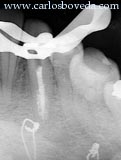

Nuestra actitud frente al caso :

En nuestra opinión, en este momento es indispensable el tratamiento de conductos en el canino inferior izquierdo, que evidencia una clara resorción interna (signo inequívoco de lesión pulpar). El canino inferior derecho evidencia una reducción significativa de su espacio pulpar, sin embargo preferimos dejar en observación periódica.

Detalle del aislamiento y abordaje del caso.

Se determina la longitud de tratamiento y se prepara de acuerdo a la condición anatómica presente, haciendo hincapié en el control y la acción de la irrigación manual y ultrasónica.

Una vez culminada la preparación, y ante la evidencia de resorción presente, se coloca Hidróxido de Calcio en el interior del diente, teniendo cuidado de cubrir la totalidad del espacio interno.

Este hidróxido se recambia un par de veces en un período de 6 semanas. El caso se mantiene asintomático.

Se decide entonces completar el tratamiento endodóntico.

Imágenes radiográficas en proyección mesio, otro y disto radial del caso culminado.